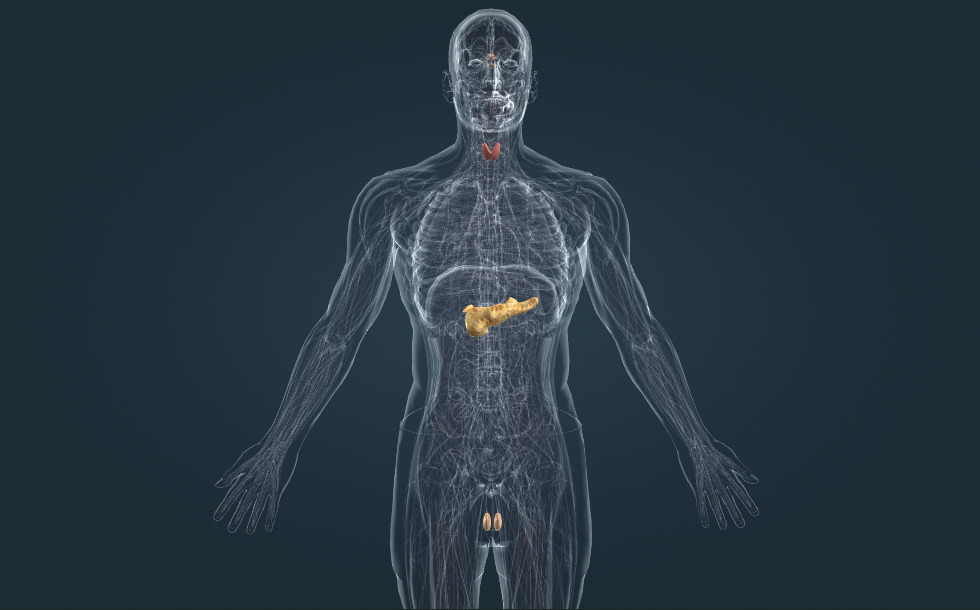

Hệ nội tiết

- tuyến cận giáp - Chúng tiết ra hormone tuyến cận giáp (parathormone), có tác dụng làm tăng nồng độ canxi trong máu. Calcitonin, do tuyến giáp tiết ra, có tác dụng ngược lại: làm giảm nồng độ canxi trong máu.

- tuyến thượng thận - Nó bao gồm phần vỏ và phần tủy. Phần vỏ tiết ra hormone làm tăng nồng độ natri và nồng độ glucose trong máu. Phần tủy sản xuất ra epinephrine (adrenaline), là một loại hormone gây căng thẳng, đóng vai trò quan trọng trong việc đáp ứng với gây căng thẳng cấp tính.

- tinh hoàn - Nó sản xuất tinh trùng và testosterone (hormone sinh dục nam), có vai trò thúc đẩy sự trưởng thành của tinh trùng, thúc đẩy sự phát triển của lông và các đặc điểm của nam giới.

- tuyến tụy - Nó tiết ra insulin, có vai trò làm giảm nồng độ glucose trong máu. Thiếu insulin gây ra bệnh tiểu đường.

- tuyến giáp - Nó tiết ra hormone T4 (tiroxine), có vai trò làm tăng quá trình oxy hóa sinh học. Nó đóng vai trò quan trọng trong sự phát triển bình thường của não và trong sự tăng trưởng bình thường của cơ thể. Việc sản xuất quá nhiều hormone tuyến giáp gây ra bệnh Graves, trong khi suy giáp gây ra bệnh bướu cổ hoặc ngu đần (gây ra bởi chứng suy giáp bẩm sinh).

- tuyến yên - Cùng với vùng dưới đồi, nó tạo nên trục vùng dưới đồi - tuyến yên, là trung tâm của hệ nội tiết.

Các tuyến của hệ nội tiết sản xuất ra các hormone. Ví dụ, Adrenaline do tuyến thượng thận tiết ra, insulin được tiết bởi tuyến tụy và thyroxine được tiết bởi tuyến giáp.

Trung tâm của hệ nội tiết là trục vùng dưới đồi-tuyến yên. Vùng dưới đồi sản xuất các hormone có vai trò điều chỉnh tuyến yên, chúng kích thích tuyến yên sản xuất hormone. Những hormone này lại kích thích các tuyến nội tiết khác: tuyến giáp, tuyến thượng thận và các tuyến sinh dục. Vùng dưới đồi-tuyến yên không điều hòa tuyến tụy.

Các tuyến của hệ nội tiết sản xuất ra các hormone. Ví dụ, Adrenaline do tuyến thượng thận tiết ra, insulin được tiết bởi tuyến tụy và thyroxine được tiết bởi tuyến giáp.

Trung tâm của hệ nội tiết là trục vùng dưới đồi-tuyến yên. Vùng dưới đồi sản xuất các hormone có vai trò điều chỉnh tuyến yên, chúng kích thích tuyến yên sản xuất hormone. Những hormone này lại kích thích các tuyến nội tiết khác: tuyến giáp, tuyến thượng thận và các tuyến sinh dục. Vùng dưới đồi-tuyến yên không điều hòa tuyến tụy.